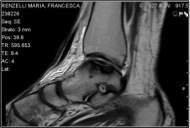

Una radiografia standard della caviglia associata ad una RM sono spesso sufficienti allo specialista ortopedico per determinare la causa del difetto cartilagineo ed impostare un corretto approccio terapeutico.